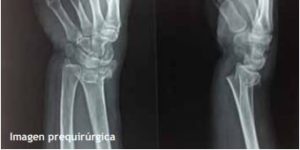

Caso 1.- Masculino de 52 años de edad con fractura de radio distal y estiloides cubital, se realizó reducción incruenta y fijación percutánea con 2 clavos de Kirschner obteniéndose una adecuada reducción y estabilidad. (fig. 2)